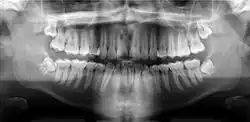

A panoramic radiograph is a panoramic scanning dental X-ray of the upper and lower jaw. It shows a two-dimensional view of a half-circle from ear to ear. Panoramic radiography is a form of focal plane tomography; thus, images of multiple planes are taken to make up the composite panoramic image, where the maxilla and mandible are in the focal trough and the structures that are superficial and deep to the trough are blurred.

Orthopantomograms (OPTs) are used by health care professionals to provide information on:

- Impacted wisdom teeth diagnosis and treatment planning - the most common use is to determine the status of wisdom teeth and trauma to the jaws.